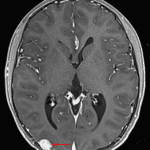

- Cortically-based T2/FLAIR hyperintense lesion in the right occipital lobe

- Associated solid nodular enhancement measuring 15 mm with corresponding mild restricted diffusion

- Overlying calvarial scalloping

- Mild local mass effect without midline shift or evidence of herniation or hydrocephalus

Ganglioglioma